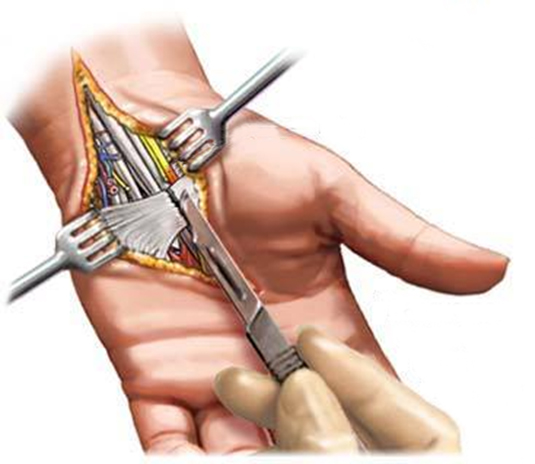

수술적 치료법

수술은 마취 하에서 손바닥 부위에 2cm의 절개를 가하여, 정중신경을 압박하는 손목 수평인대를 잘라주는 것입니다.

수평인대 절개는 피부 절개 부위에서 손목안쪽과 손가락 부위로 확장하여 정 중 신경을 누를 가능성이 있는 모든 구조물을 피부하에서 절개 하여야 합니다.

수술 후 회복의 정도는 신경의 압박 정도와 그리고 얼마나 오래 압박이 되어 있었는지 당뇨병의 유무와 밀접한 관계가 있습니다. 손저림 초기나 중기의 수술을 하신

분들은 수술 후 다음날이면 손 저림이 많이 없어져 수술의 효과가 금방 나타나기도 합니다.

그러나 이미 손바닥 근육의 힘들 이 있거나, 당뇨가 있는 경우, 그리고 너무 오랜 기간 동안 보존적 치료를 한 경우, 그리고 재발 되어 재 수술을 한 경우에는 수술을 받더라도

회복기간이 상당히 오래 걸리게 됩니다. 이런 경우에는 수술의 목적이 손저림의 완전한 치료보다는 신경압박으로 인한 증상 악화를 예방 하는 것이 더 우선적인 것입니다.

국제바로병원에서는 하루 입원 일정으로 수술 및 다음날 퇴원이 가능하며 수술 후 일주일간 손목 굽힘을 방지하는 부목을 대고, 실밥은 보통 수술 후 2주에 모두 뽑습니다.

실밥을 뽑는 후에는 더 이상 소독은 필요하지 않고, 비누로 씻고 절개부위를 연고로 마사지를 열심히 해주는 것이 좋습니다.

이렇게 하면, 상처가 빨리 부드러워지고, 절개부위의 아래에 있는 신경도 자극이 되어 회복 이 빨라집니다. 수술 후 손사용을 억제하는 것은 기능 회복에 도움이 되지 않고,

가능한 범위 내 에서 일상생활을 하는 것이 신경 재생과 손 기능 회복에 도움이 됩니다.